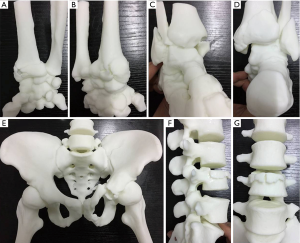

The original CT data in DICOM format from four patients, each with a different fracture type (one spinal fracture, one pelvic fracture, one upper limb fracture, and one lower limb fracture), were obtained from the Star PACS system (INFINITT, Seoul, South Korea) of our hospital (3). All the data were imported into the software Mimics 16.0 (Materialise, Belgium). The threshold value was set at “Bone (CT)” to reconstruct the 3D images. After the 3D digital images were calculated and reconstructed (26), the data were then saved in STL format and imported into the 3D printer (Liantai, Shanghai) (27). All of the fractures described above were transformed into 3D printed models and preserved for education.

For the traditional radiographic image group, the lecture was presented using PowerPoint and included normal anatomy, the definition of fractures, and the presentation of the fractures on X-ray and CT. Before the presentation to the 3D printed model group, students were paired, and each pair received four different fracture models (one spinal fracture, one pelvic fracture, one upper limb fracture, and one lower limb fracture). Students in this group learned from a combination of PowerPoint and the visible 3D printed models.